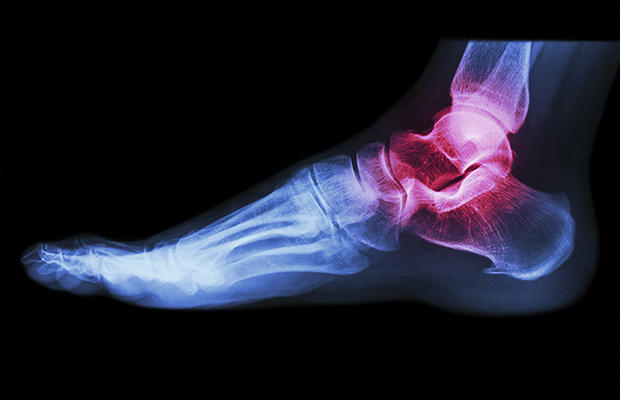

إلتهاب المفاصل

تحتوي قدميك على أكثر من 30 مفصل، والتي يمكن أن تتدهور مع التقدم في السن. التهاب المفاصل الأكثر شيوعا يصيب إصبع القدم الكبير أو مفصل أوسط القدم في الجزء العلوي من قدمك. وإلى جانب شعورك بالألم، قد تشعر بالتصلب في الصباح بمجرد أن تتحرك، ثم يزداد سوءا مرة أخرى في الليل. قم بتمارين لزيادة الحركة، و افقد بعض الوزن إذا كنت تعاني من الوزن الزائد.

التهاب الورك و مفاصل الركبة أيضا يمكن أن يسبب الألم داخل أو خارج قدميك. إذا كنت تشعر بآلام المفاصل، توجه إلى الطبيب, فمع ممارسة الرياضة أو الأدوية غالبا ما يخف الحمل على قدميك.